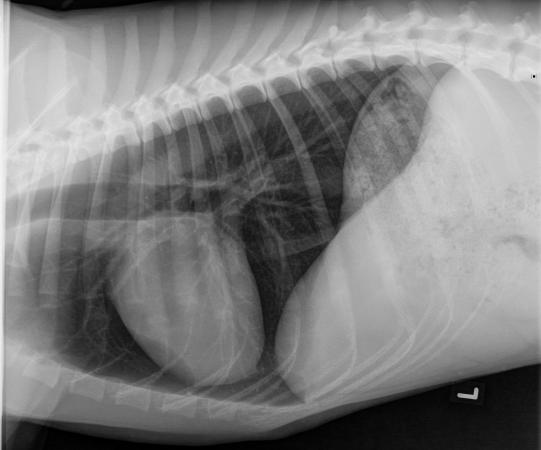

In der Praxis ist der sonst sehr lebhafte Rüde aussergewöhnlich ruhig, frisst aber angebotene Leckerli. Er atmet verstärkt und zeigt eine erhöhte Körpertemperatur von 39.7 °C (normal: 38-39 °C). Die Milz fühlt sich sehr gross an; der restliche Untersuch ist unauffällig. Das zunehmend schlechtere Befinden erfordert eine rasche Abklärung, weshalb dem Hund Blut abgenommen wird und wegen der verstärkten Atmung eine seitliche Röntgenaufnahme der Brust sowie ein kurzer Bauchultraschall zur Beurteilung der Milz durchgeführt werden.

Das Bruströntgen ist unauffällig; die verstärkte Atmung dürfte also aufgrund des Fiebers und durch die (aufgrund der fehlenden roten Blutkörperchen) reduzierte Sauerstofftransport-Kapazität des Blutes zustandekommen. Im Bauchraum findet sich keine Flüssigkeit; und abgesehen von der Grössenzunahme erscheint die Milz unauffällig.